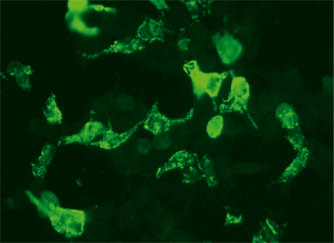

The diagnosis of autoimmune encephalitides is generally based on a combination of the characteristic clinical picture, supporting findings from brain MRT, EEG and CSF analysis if necessary, and antibody determination in serum/CSF. Monospecific recombinant assays are the method of choice for serological diagnostics and can be combined with conventional immunohistochemical detection procedures. The following conditions must be excluded by differential diagnostics: infectious encephalitides (especially HSV), other autoimmune aetiologies (e.g. limbic encephalitis with autoantibodies against Hu, Ma2, CV2, amphiphysin) and clinically similar diseases of the central and/or peripheral nervous system. A diagnostic discrimination from atypical encephalitides should also be taken into consideration. It should be taken into account that overlap syndromes and combinations of different syndromes can also occur. When a positive serological result is obtained, a comprehensive tumour investigation should be undertaken.

The diagnosis of autoimmune encephalitides is generally based on a combination of the characteristic clinical picture, supporting findings from brain MRT, EEG and CSF analysis if necessary, and antibody determination in serum/CSF. Monospecific recombinant assays are the method of choice for serological diagnostics and can be combined with conventional immunohistochemical detection procedures. The following conditions must be excluded by differential diagnostics: infectious encephalitides (especially HSV), other autoimmune aetiologies (e.g. limbic encephalitis with autoantibodies against Hu, Ma2, CV2, amphiphysin) and clinically similar diseases of the central and/or peripheral nervous system. A diagnostic discrimination from atypical encephalitides should also be taken into consideration. It should be taken into account that overlap syndromes and combinations of different syndromes can also occur. When a positive serological result is obtained, a comprehensive tumour investigation should be undertaken.

The diagnosis of autoimmune encephalitides is generally based on a combination of the characteristic clinical picture, supporting findings from brain MRT, EEG and CSF analysis if necessary, and antibody determination in serum/CSF. Monospecific recombinant assays are the method of choice for serological diagnostics and can be combined with conventional immunohistochemical detection procedures. The following conditions must be excluded by differential diagnostics: infectious encephalitides (especially HSV), other autoimmune aetiologies (e.g. limbic encephalitis with autoantibodies against Hu, Ma2, CV2, amphiphysin) and clinically similar diseases of the central and/or peripheral nervous system. A diagnostic discrimination from atypical encephalitides should also be taken into consideration. It should be taken into account that overlap syndromes and combinations of different syndromes can also occur. When a positive serological result is obtained, a comprehensive tumour investigation should be undertaken.

The diagnosis of autoimmune encephalitides is generally based on a combination of the characteristic clinical picture, supporting findings from brain MRT, EEG and CSF analysis if necessary, and antibody determination in serum/CSF. Monospecific recombinant assays are the method of choice for serological diagnostics and can be combined with conventional immunohistochemical detection procedures. The following conditions must be excluded by differential diagnostics: infectious encephalitides (especially HSV), other autoimmune aetiologies (e.g. limbic encephalitis with autoantibodies against Hu, Ma2, CV2, amphiphysin) and clinically similar diseases of the central and/or peripheral nervous system. A diagnostic discrimination from atypical encephalitides should also be taken into consideration. It should be taken into account that overlap syndromes and combinations of different syndromes can also occur. When a positive serological result is obtained, a comprehensive tumour investigation should be undertaken.